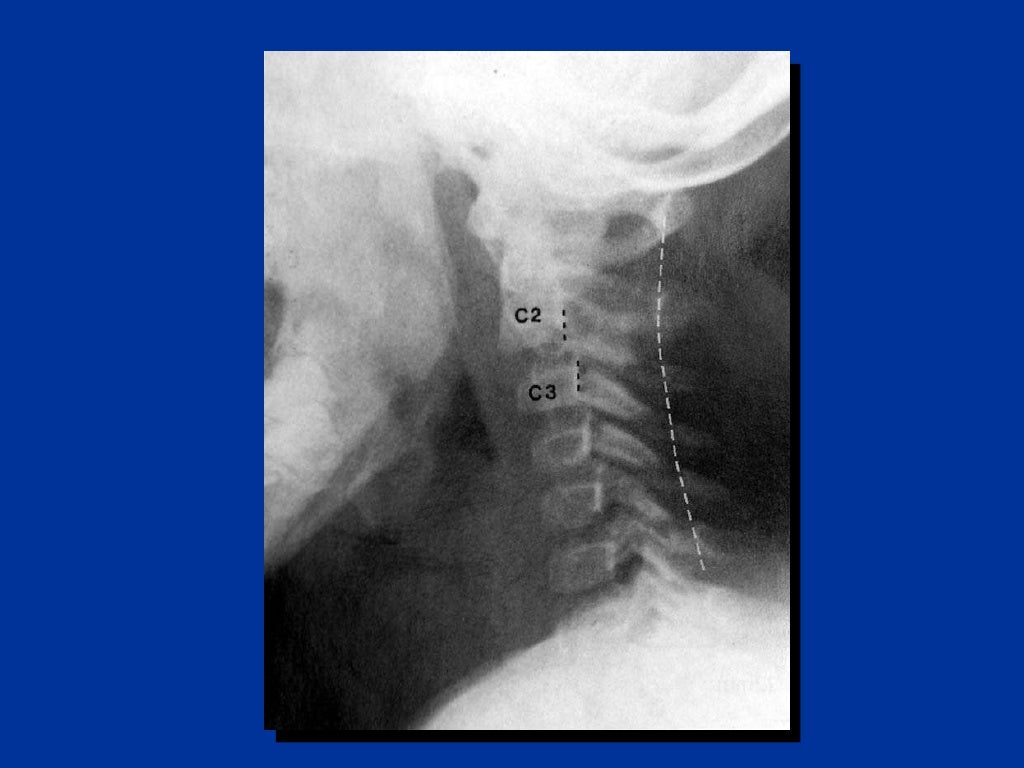

X-ray consists of a three view cervical x-ray series, adding a swimmer's view if the lateral doesn't include the C7/T1 interface.

CT scan or X-ray images are evaluated for the presence or absence of directly visible fractures. In addition, indirect signs of injury by the vertebral column are incongruities of the vertebral lines, and/or increased thickness of the prevertebral space: